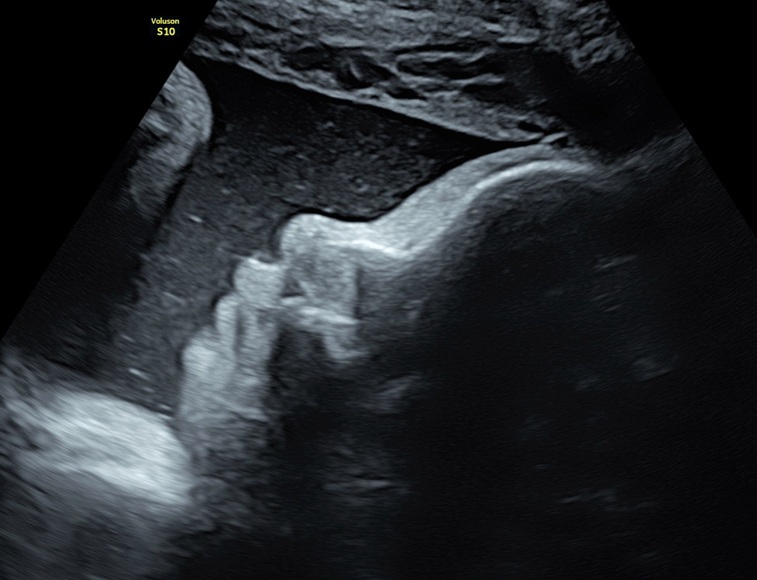

Tijdens de tussendoorecho krijg je een beeld van je baby in 2D. Een tussendoor echo kan in principe de gehele zwangerschap vanaf 8 weken, na 32 weken is vaak het gezicht van je baby niet zo goed meer in beeld te brengen. Bij een vroege echo’s <11 weken wordt er niet geluisterd naar de hartslag van de baby. Natuurlijk ontvang je een aantal foto’s als herinnering.